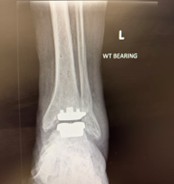

The latest data shows that ankle replacement survivorship and patient outcomes have improved significantly in recent years.

With modern implants, better surgical techniques, and refined rehabilitation pathways, patients are achieving excellent long-term mobility and comfort.

For others with more advanced arthritis, today’s ankle replacement techniques can restore movement and reduce pain while keeping the joint flexible something fusion can’t offer.